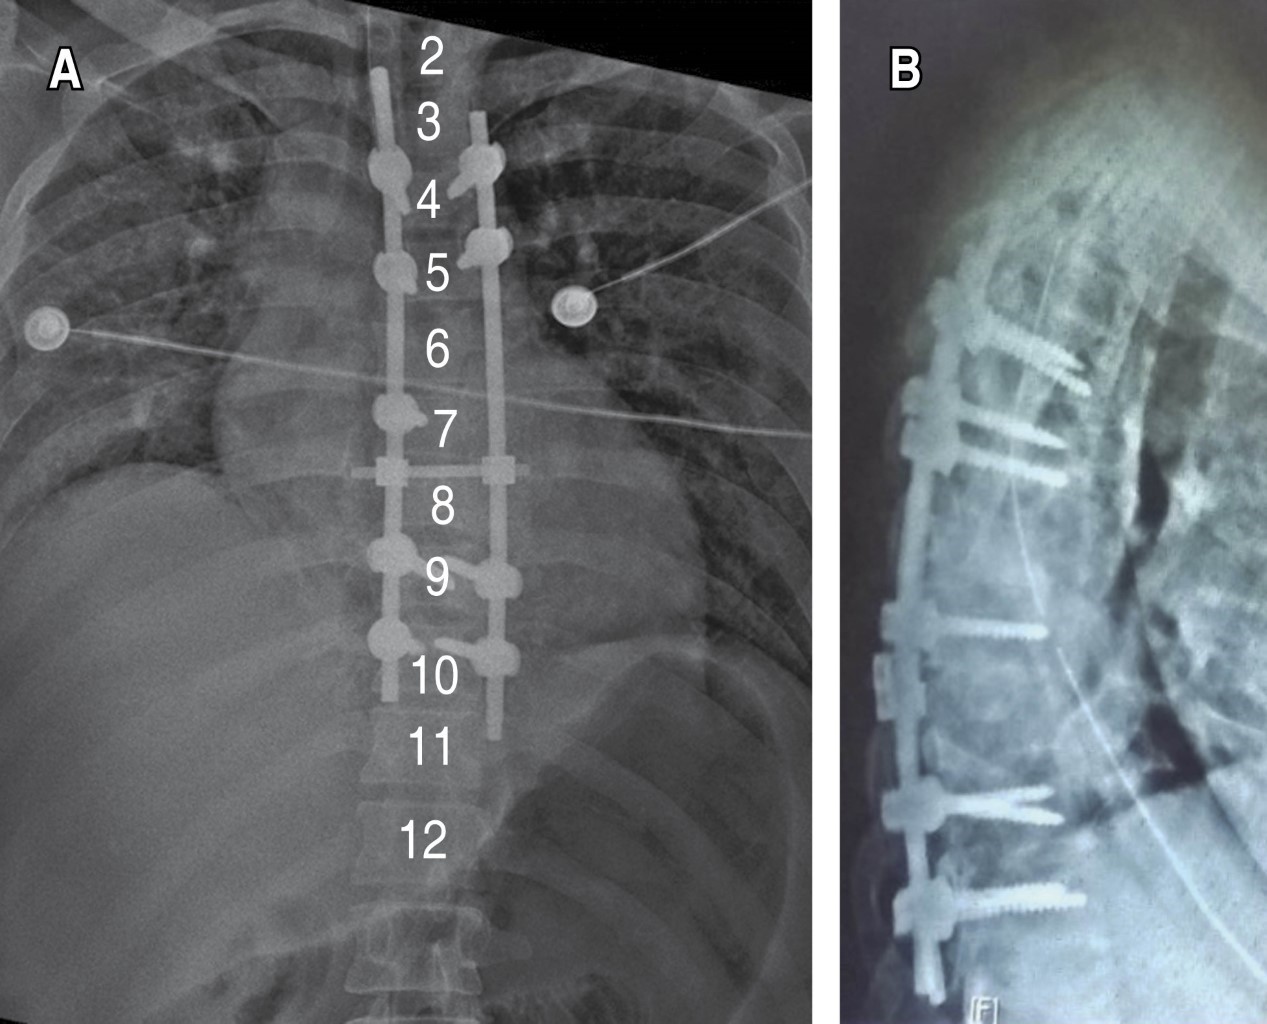

Figure 3